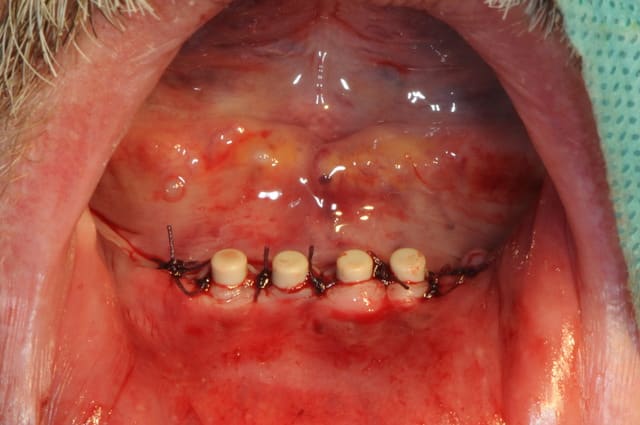

Bon, je viens de lui poser ses 4 mini-implants ce matin.(diamètre2.8 longueur 13mm)

je crois que comme ils ne sont pas trop mal disposées, je vais les solidariser par une barre d'Ackerman plutôt que 4 boules.

Pour les 4 minis implants, au moins c'est pas du 2.0 mm

Petite remarque, je trouve que les implants sont trop en ligne, pas assez de distribution antéro-postérieur. Placés sur une courbe, on a une meilleur distribution des forces.

Aussi, aurait-il été possible de les placer plus distalement ?

Pourquoi pas placer 4 implants 3,8 mm avec une légère plastie verticale ? La chirugie est 95 % la même.